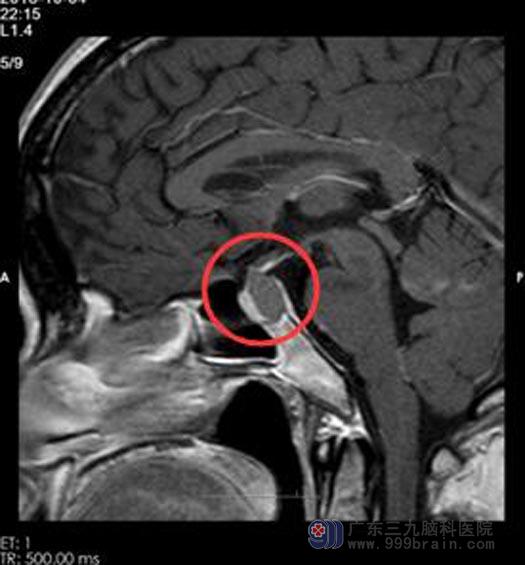

在家人的劝说下,去医院进行了检查,颅脑MRI提示:鞍区占位性病变。

手术前